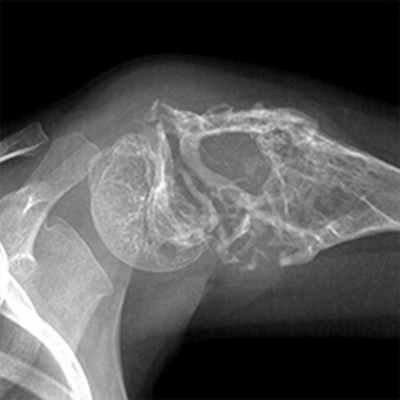

Хондросаркомы могут поражать любую кость скелета, однако преобладающей локализацией опухоли являются кости таза и бедренная кость. Нередко хондросаркома развивается в плоских костях, таких как лопатка, ребра, кости таза и черепа. Клиническое течение ходндросарком относительно медленное, но встречаются и быстрорастущие варианты заболевания.

Метастазы хондросаркомы развиваются в относительно поздние сроки. Для клинической картины характерно возникновение болей в пораженной области. При поражении костей таза симптомокомплекс включает в себя картину вовлечения нервных корешков, заключающийся в болевом синдроме и нарушении функции тазовых органов.

Рак простаты чаще бывает бластным, рак легкого – литическим, а рак молочной железы может быть бластным или литическим.